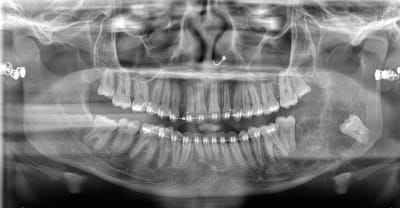

comme promis

Pour info, c'est quoi tous ces petits éléments qui trainent autour de l'angle mandibulaire ?

Des agrafes ?

01/10/2025 à 07h31

Tout est allé très vite pour elle.

Même l’edification radiculaire des dents de sagesse en l’espace d’une année est surprenante 🤔

Moi ce qui m'impressionne c'est le déplacement de la 38.